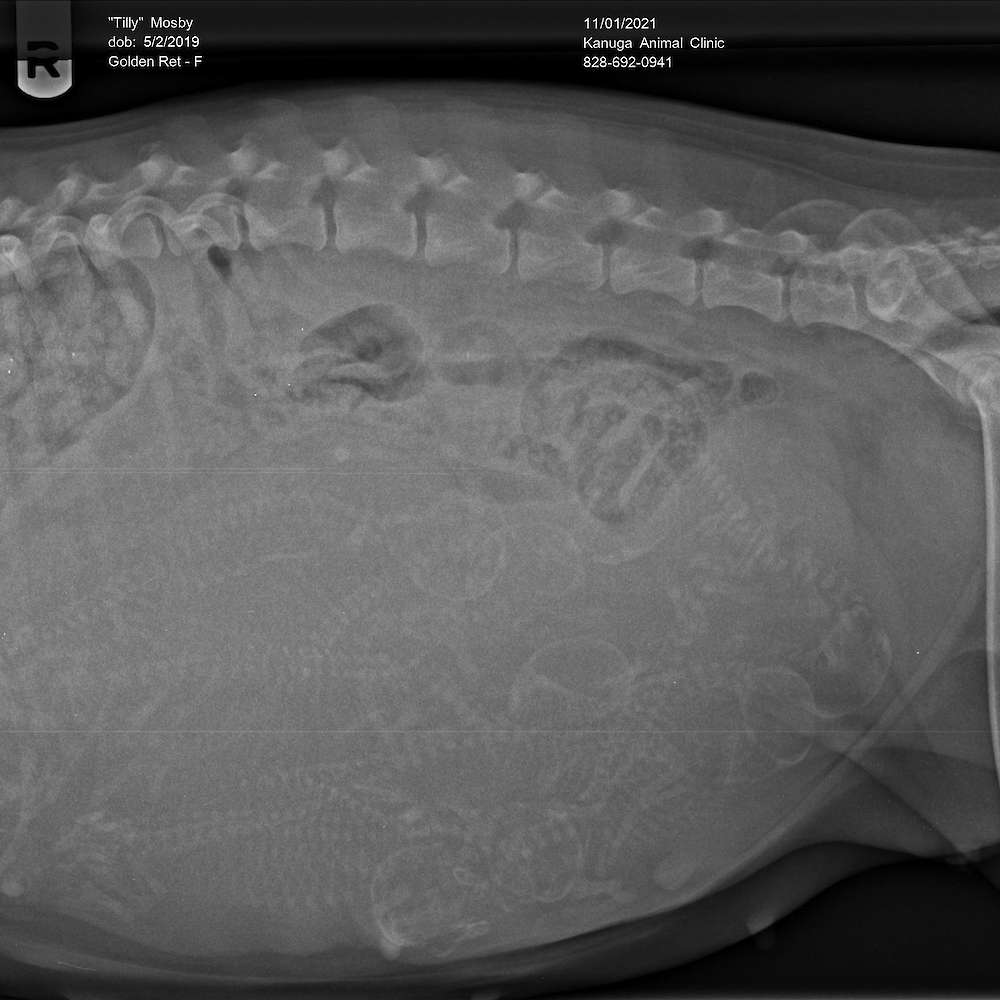

Tilly X Cowboy

5 November 2021